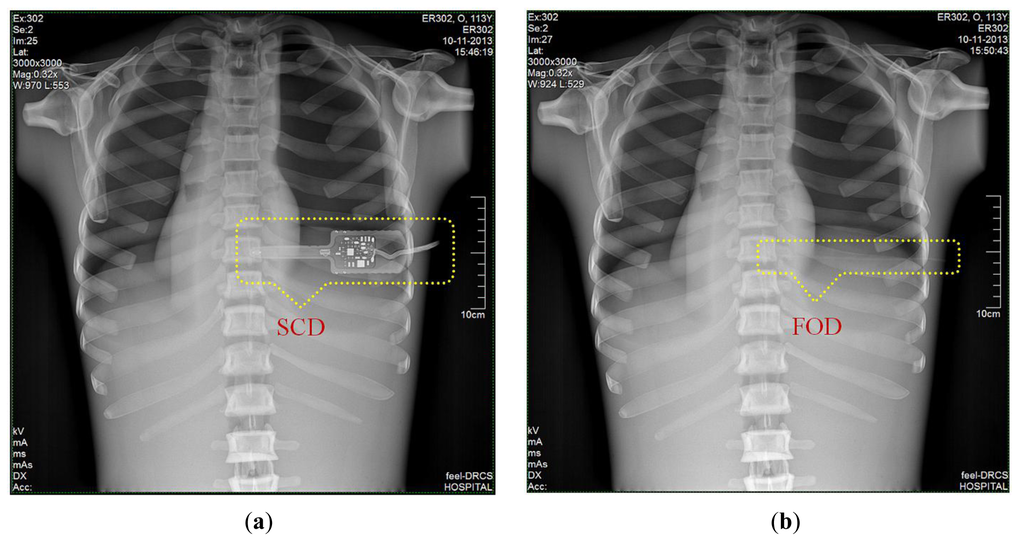

3.6. DR Images of Anthropomorphic Thorax Phantom

Finally, we obtained DR images from a posteroanterior (PA) chest examination using a flat panel detector of the DR system. In this evaluation, the values of the tube potential, current-time product (tube current x irradiation time), FID, and field size were set at 110 kVp, 10 mAs (320 mA × 32 ms), 180 cm, and 30 × 30 cm2, respectively. Figure 9a,b shows two DR images of the anthropomorphic thorax phantom with the finger-shaped dose sensor of the SCD and the sensing probe of the FOD, respectively. To measure real-time ESD and to evaluate the effects of the dosimeter on the image artifacts during PA chest radiography, each distal end of two different dosimeters was placed sequentially at the center of the beam field on the thorax phantom. As can be seen in Figure 9a, the SCD caused image artifacts due to its large size and high-atomic-number materials and, accordingly, the image interfered with the examination of radiation imaging. On the other hand, the FOD makes it possible to measure the ESD with minimization of image artifacts, as shown in Figure 9b, because its size is very small compared to the SCD and it consists of low-atomic materials (i.e., near tissue-equivalent materials) [5]. Particularly, we can expect that the constituent materials of the sensing probe will attenuate X-ray photons in a similar way as the density and atomic compositions of the PSF, POF, and black jacket are quite well matched [22,23].